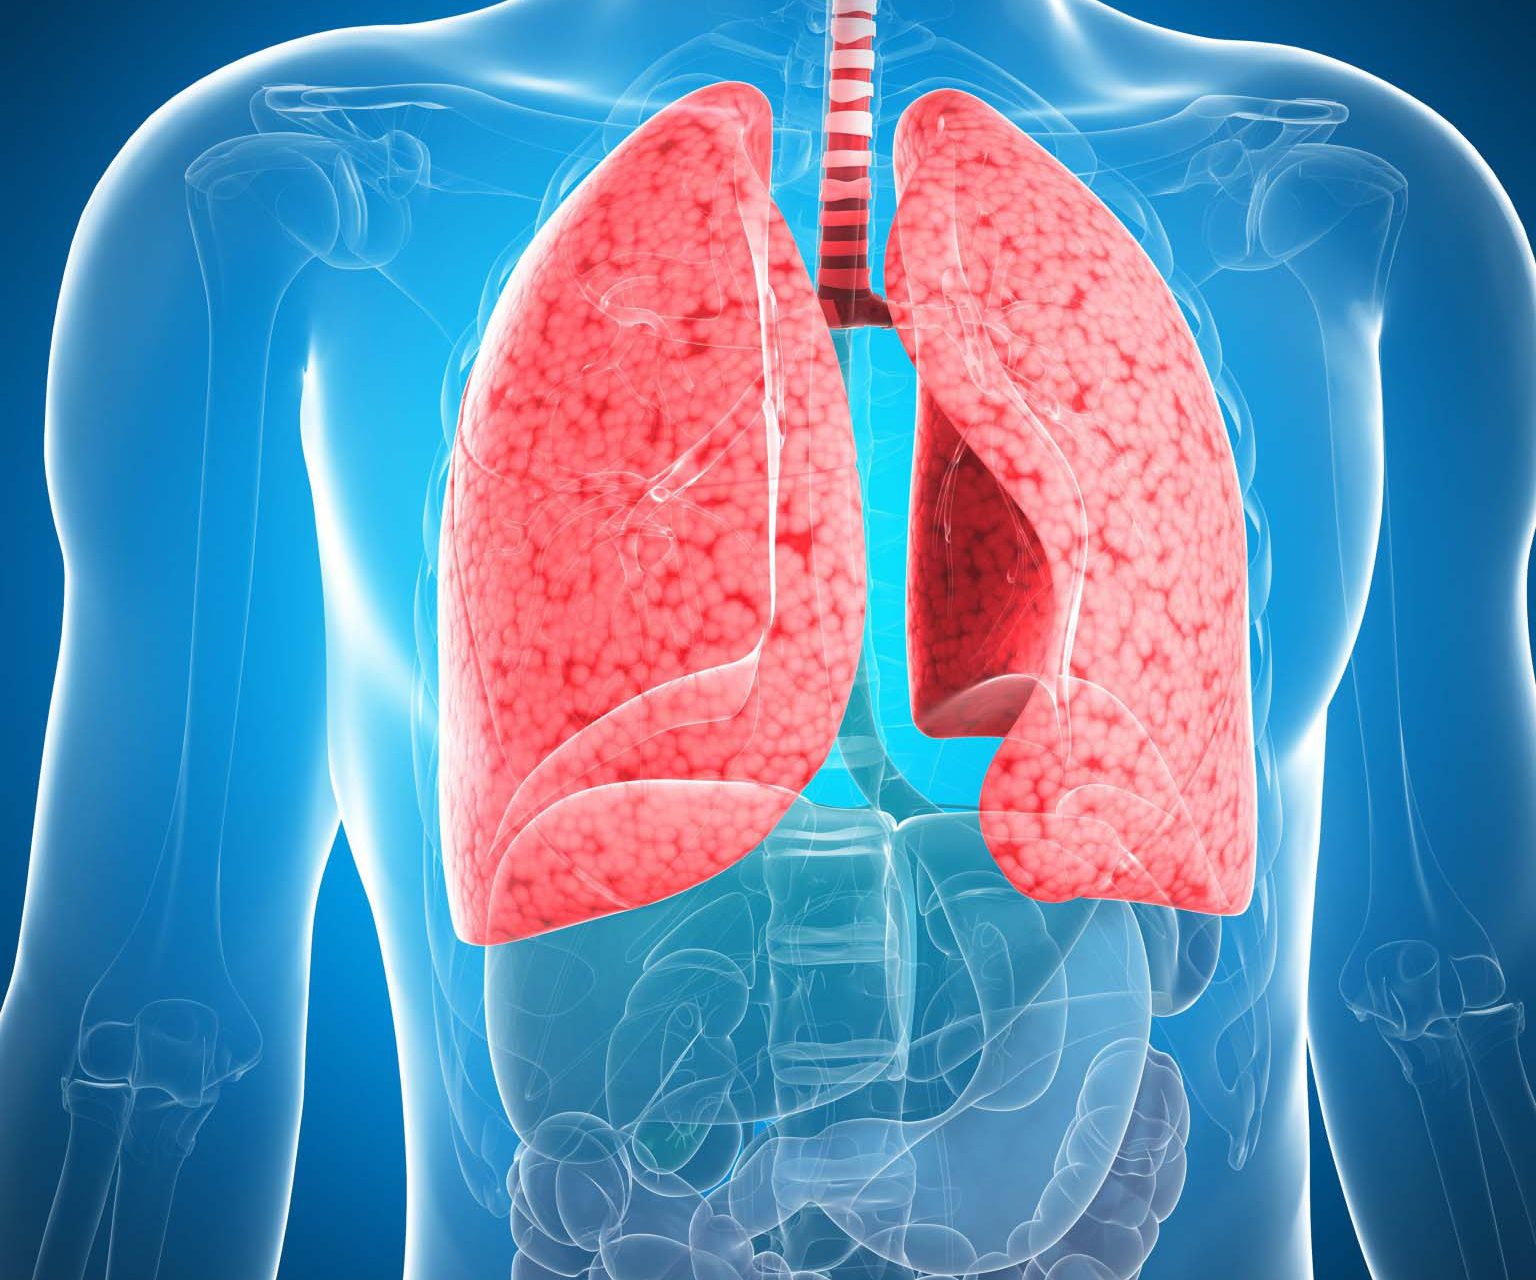

Лёгкие человека: Учебные картинки для детей